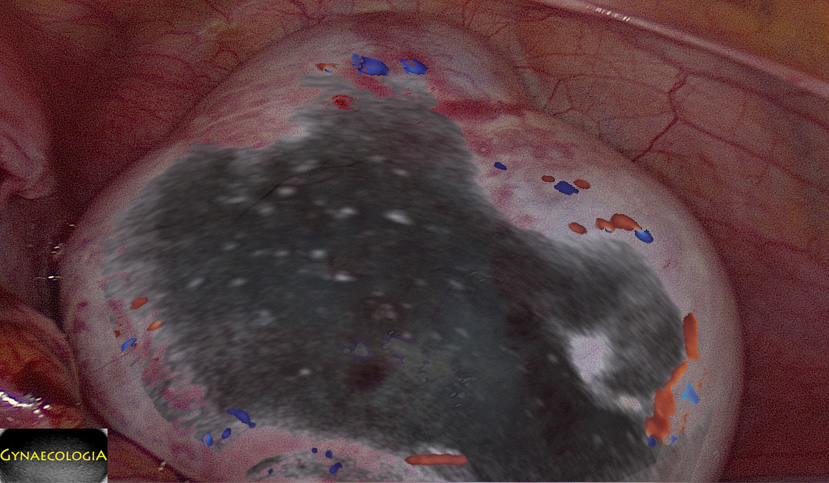

Ultrasound findings

- Frequently large, unilateral, cystic mass.

- Usually multilocular.

- Smooth walls.

- Contains small cystic components or honeycomb-like loculi.

- Intralocular fluid of varying echogenicity.

- Linear calcifications (rare).

- Papillary projections (rare).

- Mucinous ascites may present after cyst rupture.

From a pathology point-of-view, don’t forget that concomitant findings may include Brenner tumors, teratomas, and sarcoma-like mural nodules adding their respective ultrasound findings. (Mills A.M. & Shanes E.D., 2019).